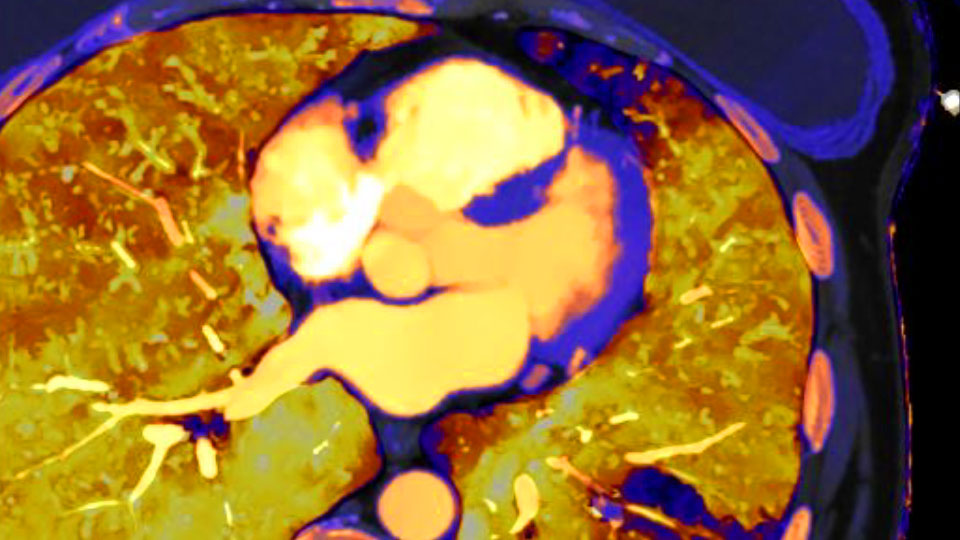

Aumente e desenvolva sua capacidade em exames cardíacos com imagens espectrais e um campo de visão completo. Reduza artefatos de blooming de cálcio nas artérias coronárias.